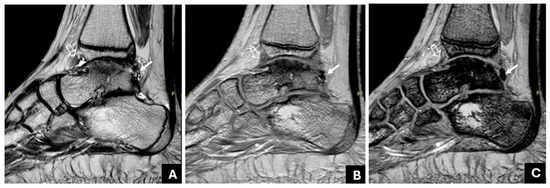

- Akyuz, B.; Polat, A.V.; Ozturk, M.; Aslan, K.; Tomak, L.; Selcuk, M.B. Contribution of 3-T susceptibility-weighted MRI to detection of intraarticular hemosiderin accumulation in patients with hemophilia. AJR 2018, 210, 1141–1147. [Google Scholar] [CrossRef]

- Zhang, L.; Wei, S.; Li, J.; Wang, P.; Ge, Y. Value of 3.0T MRI T2 mapping combined with SWI for the assessment of early lesions in hemophilic arthropathy. Hematology 2022, 27, 1263–1271. [Google Scholar] [CrossRef] [PubMed]

- Prasetyo, M.; Mongan, A.E.; Chozie, N.A.; Prihartono, J.; Setiawan, S.I. Hemosiderin deposition evaluation in hemophilic ankle joints: Association between US finding and gradient-recalled echo MR imaging sequence. Insights Imaging 2021, 12, 107. [Google Scholar] [CrossRef]